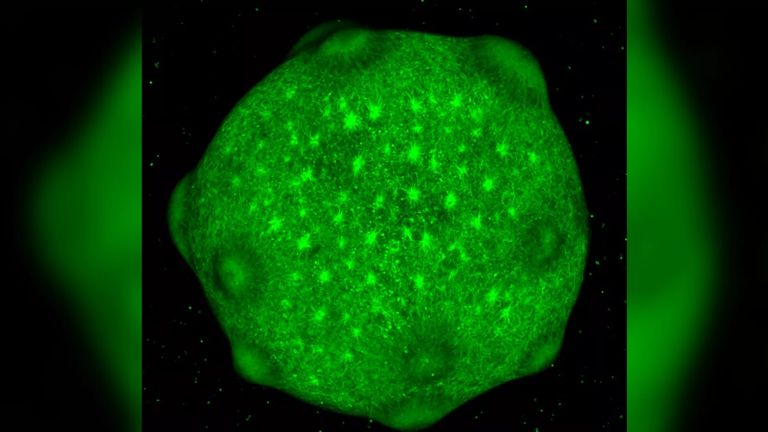

وذكرت الصحيفة أن عضويات الدماغ هي عبارة عن كتل صغيرة من الخلايا الجذعية تعيش في أطباق المختبر والتي تم دمجها في هياكل ثلاثية الأبعاد تحاكي بنية ووظيفة الدماغ البشري، ولكنها أبسط من العضو بالحجم الكامل.

وأشارت الصحيفة إلى أن العضويات تشترك في العديد من أنواع الخلايا التي تمكن أدمغتنا من الحصول على المعلومات وتخزينها، ويقول الباحثون إن نقاط الدماغ مناسبة بشكل فريد للمهام الحسابية التي تتطلب منهم التعلم بسرعة ودون إنفاق الكثير من الطاقة، قبل تخزين المعلومات بعيدا في اتصالات عصبية مضغوطة، بحسب مجلة "لايف ساينس" العلمية.